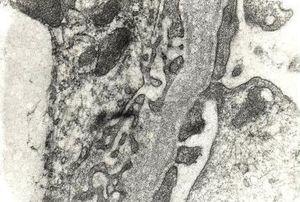

MCD was the second most frequent lesion underlying NS in children in this study. It used to be the leading cause of INS in children, but many researchers have found a declining prevalence of this lesion throughout the world in recent years.9 The EM study was essential for the diagnosis of this disease, in that it demonstrated the most important morphological lesion of the disease, i.e., the fusion of foot processes. Although, the diagnosis of MCD can be suspected on LM and IF examinations, it is only the EM study that conclusively establishes its diagnosis, as shown in Figure 1. We acknowledge the fact the potential role of EM in establishing a diagnosis of MCD in a pediatric population is not without controversy, especially, in the perspective of developing countries. The definitions of essential and helpful roles of EM have been derived from studies done in developed countries, and may not be equally relevant for resource constrained developing countries. It could be argued that children presenting with nephrotic-range proteinuria and a normal appearing renal biopsy on LM could be presumed to have MCD. By this argument, EM would not be essential in establishing a diagnosis of MCD. Nevertheless, standard of care in Western countries would dictate that EM is deemed essential.

Figure 1. Portions of two capillary loops showing extensive fusion of foot processes in a case of minimal change disease.